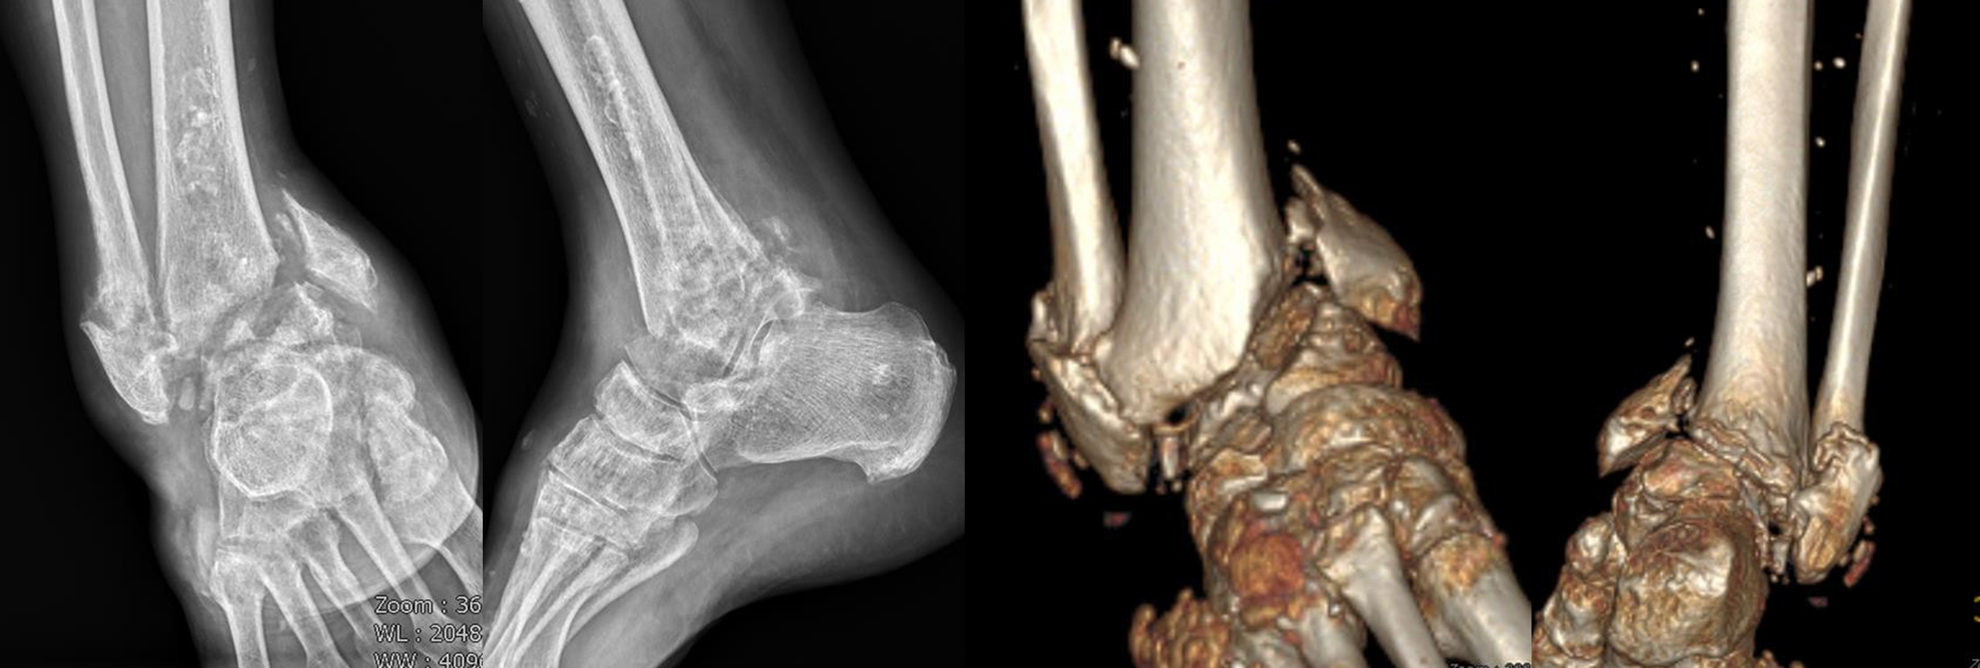

【治療前】陳舊骨折合併畸形

52 歲男性病人,本身有痛風及糖尿病。今年五月右腳踝骨折後未接受適當治療,逐漸導致骨折癒合錯位(malunion)、關節變形(deformity)以及距骨塌陷(talus collapse),行走疼痛明顯、生活品質大幅下降。